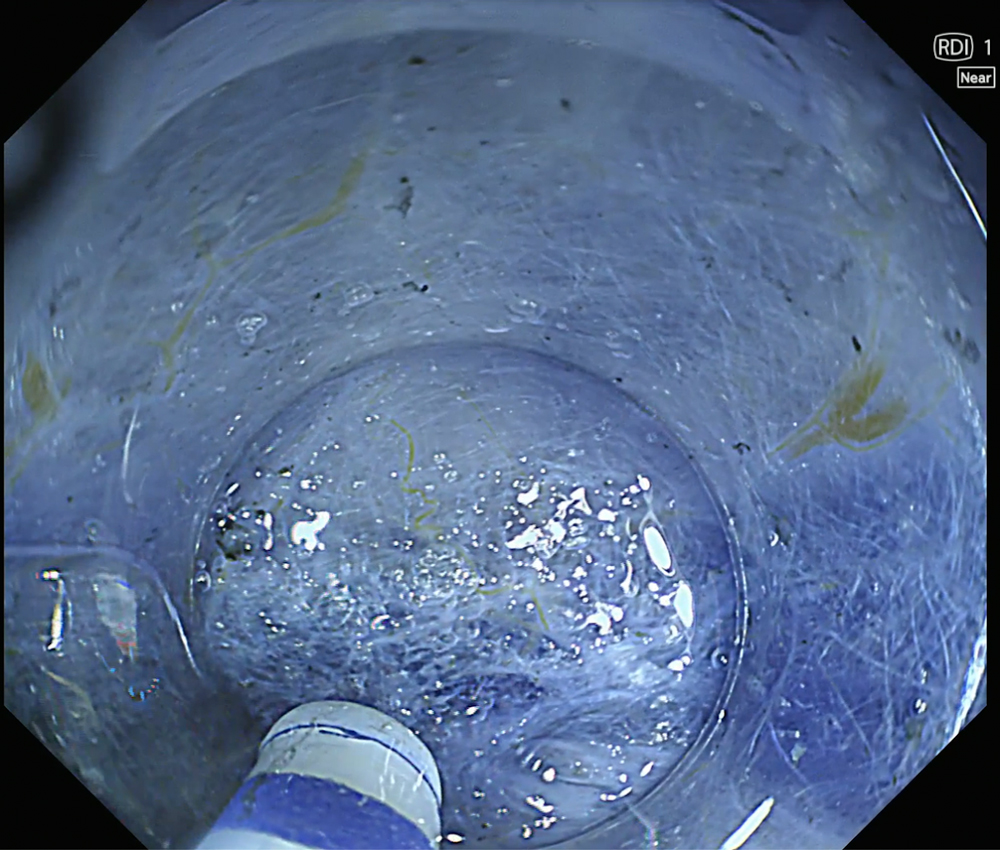

8. NBI with magnification (Near focus)

Magnified NBI with near-focus observation more clearly demonstrates focal irregular surface and vascular patterns, consistent with a JNET type IIb pattern.

Enhancement : A8

NBI Mode : On (Near focus)

TXI Mode : NA

RDI Mode : NA

BAI-MAC : On